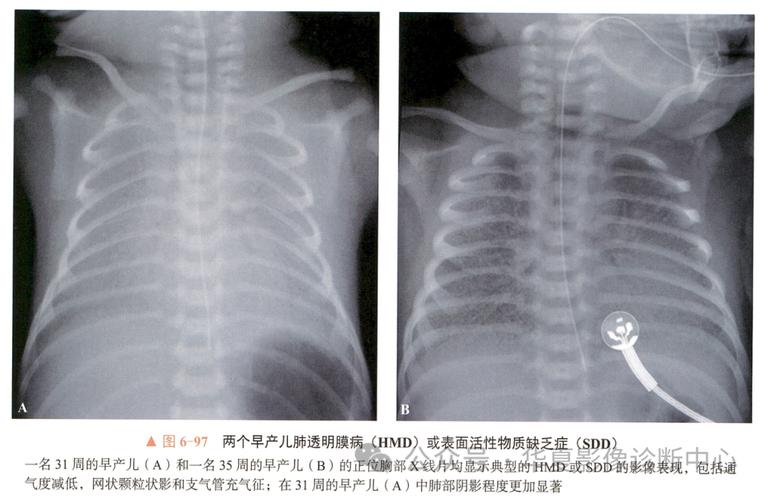

X光胸片: 这是诊断NRDS的金标准。

(图片来源网络,侵删)- 早期(I期): 两肺广泛颗粒网状阴影,肺充气差,支气管充气征明显。

- 中期(II期): 病变加重,呈“白肺”样改变,心影模糊,支气管充气征更显著。

- 晚期(III-IV期): 严重时,整个肺野呈均匀的致密影,即“白肺”,心影看不清,可能合并气胸、纵隔气肿等。